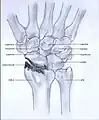

Post-traumatic osteoarthritis can be classified into four stages.[1][6] These stages are similar between SLAC and SNAC wrists. Each stage has a different treatment.

- Stage IV: the osteoarthritis is located in the entire radiocarpal joint and in the intercarpal joints. It also may involve the distal radio-ulnar joint (DRUJ).

Stage IV